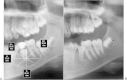

The aim of this study was to evaluate spontaneous bone regeneration after cysts enucleation of the jaws without the use of bone grafting materials. We included 18 patients at random (11 men and 7 women) with a mean age of 31.8 years, with jaw cysts treated by enucleation, without the use of grafting materials. A method of measurements to assess the percentage of reduction of the bone cavities was used to objectify the results. The patients were evaluated before and at least 6 months after surgery, with radiographic scans based on linear measures with a computerized method using Nemoceph program (Nemotec, NemoCeph Software, Madrid, España). The analysis of the sample shows an average of 85.59% decrease in horizontal measures, 89.53% in the vertical, and 88.98 and 89.81% in the diagonal left and right, respectively. The total average reduction was 88.47%. It showed a greater decrease in vertical and diagonal measurements with respect to horizontal. Regeneration in 12 patients was 100% and in 6 patients was higher at 50.4%. Bone density increased in the postoperative radiographs. The results suggest that in some cases, spontaneous bone regeneration can be achieved by cysts enucleation without bone grafting materials.